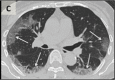

In this retrospective study, chest CTs of 121 symptomatic patients infected with coronavirus disease-19 (COVID-19) from four centers in China from January 18, 2020 to February 2, 2020 were reviewed for common CT findings in relationship to the time between symptom onset and the initial CT scan (i.e. early, 0-2 days (36 patients), intermediate 3-5 days (33 patients), late 6-12 days (25 patients)). The hallmarks of COVID-19 infection on imaging were bilateral and peripheral ground-glass and consolidative pulmonary opacities. Notably, 20/36 (56%) of early patients had a normal CT. With a longer time after the onset of symptoms, CT findings were more frequent, including consolidation, bilateral and peripheral disease, greater total lung involvement, linear opacities, "crazy-paving" pattern and the "reverse halo" sign. Bilateral lung involvement was observed in 10/36 early patients (28%), 25/33 intermediate patients (76%), and 22/25 late patients (88%).